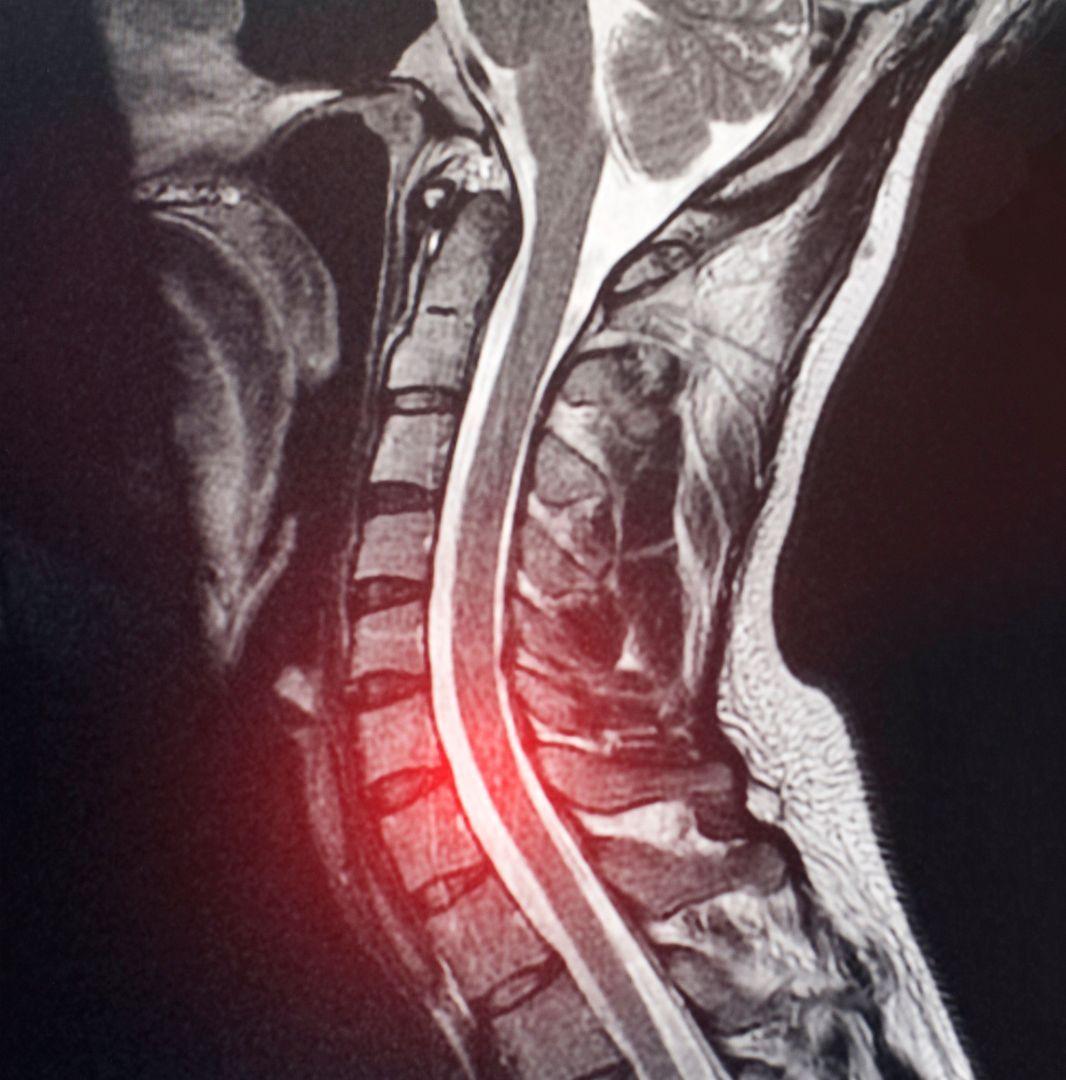

At Deuk Spine Institute, we don't just treat symptoms – we cure the source with our revolutionary Deuk Laser Disc Repair®, the world's most advanced laser spine surgery. With a 95% success rate and patients walking out pain-free within hours, we've redefined what's possible in spine care. Read our blog to learn more about root causes of pain and treatment solutions.